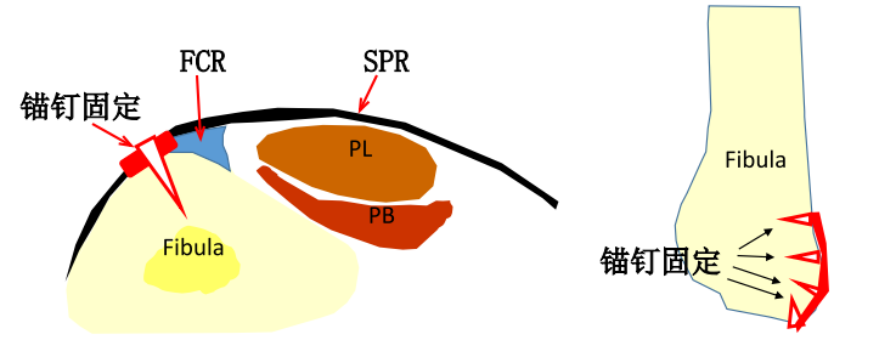

纤维软骨脊(FCR):腓骨外踝窝的外侧缘有一纤维软骨形成的缘,构成了窝的结构。该纤维软骨脊近端明显,向远端渐变小,使得沟的整体深度增加了2-4mm,且形状更适于容纳腓骨肌腱,从而促进应力分散。

腓骨上支持带(SPR):起于腓骨外侧面和腓骨外踝窝,绕过腓骨肌腱后止于跟骨和跟腱外侧。SPR没有直接牢固固定于纤维软骨脊,而是与腓骨外侧面的骨膜融合。

如不合并其他病理改变,可将支持带和骨膜直接缝合于外踝骨质上。

SPR撕脱开放手术锚钉修复

通过切除腓骨后方部分骨质,可以加深腓骨沟,改变、并增加了腓骨肌腱的稳定。

大部分急性损伤可以使用直接缝合修复,对慢性损伤则需根据患者的具体病理改变选择,如单纯的支持带结构损伤,可以直接缝合修复。如果直接修复不够稳定,需用其他组织加强。如果腓骨外踝窝较浅时,就需要使用加深手术。